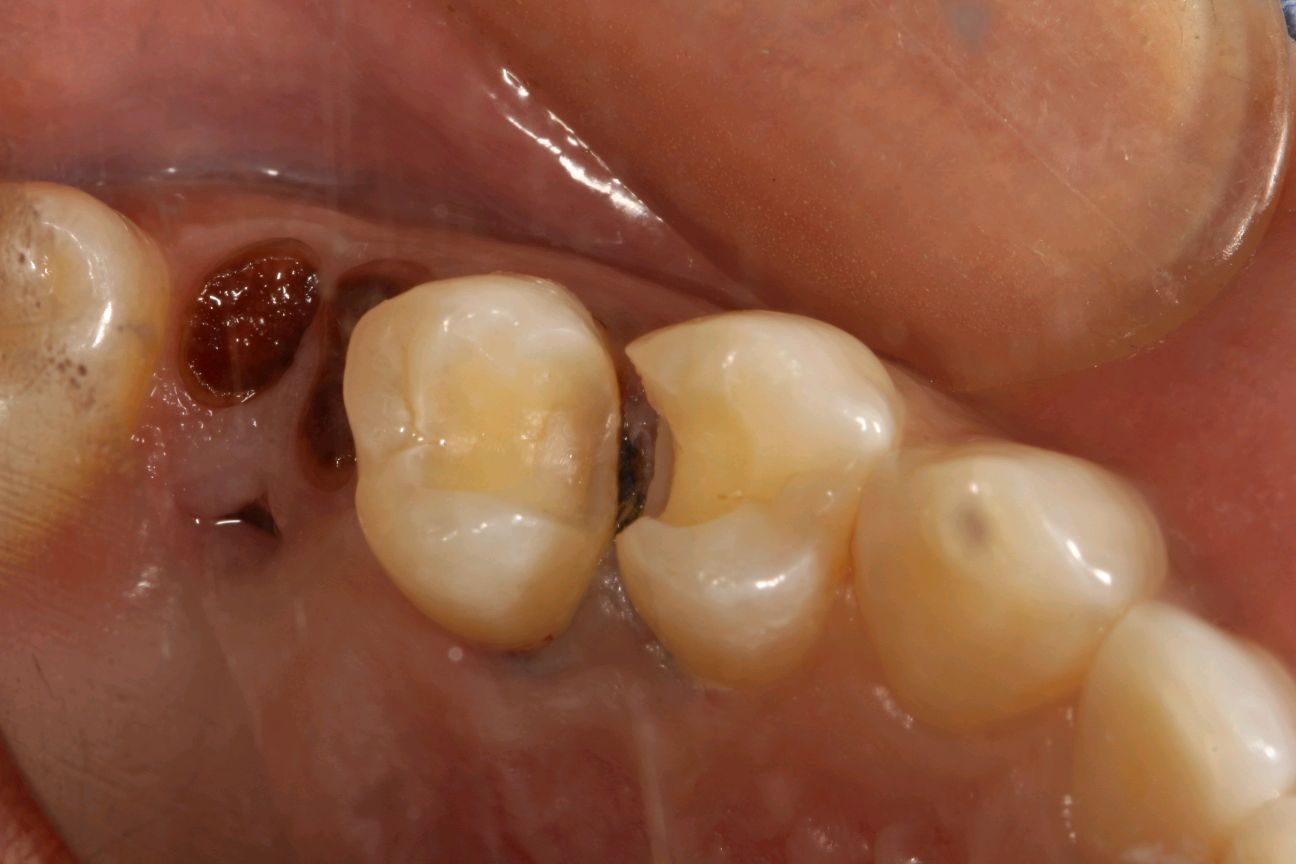

患者女,34岁,24、25邻面龋坏。经患者同意去腐备洞行嵌体修复。后通过德国 CEREC 技术扫描后,数据分析精准有效,"量身定做"专属于自己的修复体。患者当天即可配戴,既保证了边缘的密合性,还确保了色泽和形态的美观。患者不会有很强的异物感和咬合的不适。大大提高了工作的效率,也节省了患者的时间。

术中